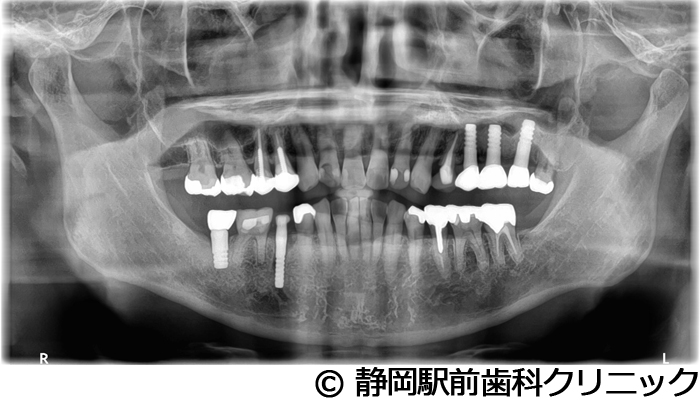

【症例4】全顎的インプラントとセラミックによる審美補綴

- 治療前

- 治療後

- 治療名

- 全顎的インプラントとセラミックによる審美補綴

- 費用

- 1,200,000円(税込)

- 期間

- 1年3ヵ月

治療内容

-

患者様の症状

左上ブリッジが歯根破折してしまい、他院で入れ歯を作ったが使い心地がよくないため、インプラント治療希望。

治療方法

抜歯後、骨治癒後にCTを撮影して、綿密に治療計画を立てた。上顎洞の距離やインプラント同士のバランスを熟慮し、インプラントを埋入した。全体的な噛み合わせの調整を重ねた後、人工歯を被せて咬合と見た目の回復を行った。

治療結果

入れ歯のような違和感が全くなく、力を入れてしっかり噛むことができるので、食事することが楽しくなったとご満足いただけました。見た目もセラミックの歯が入ったので、自分の歯が戻ったようだと喜んでいただきました。

※治療結果は個人差があります。

治療を行う上での注意点(リスク・副作用)

術後は、出血、腫れ、痛みなどが出る可能性があります。